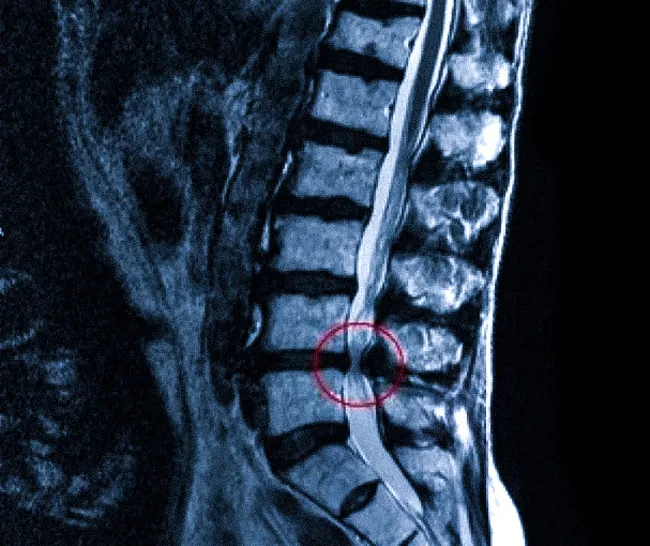

- Магнитно-резонансная томография (МРТ): МРТ плечевого сплетения и шейного отдела позвоночника позволяет визуализировать нервные структуры, выявить отёки, гематомы, компрессию нервов опухолями или грыжами межпозвонковых дисков, а также увидеть отрывы корешков от спинного мозга. МРТ с контрастированием может быть особенно информативна для оценки состояния нервных корешков и самого плечевого сплетения.

- Компьютерная томография (КТ) с миелографией: Иногда используется для более детальной визуализации спинного мозга и нервных корешков, особенно если есть подозрение на отрыв корешков. Контрастное вещество вводится в спинномозговой канал, что позволяет увидеть дефекты заполнения, указывающие на авульсию.